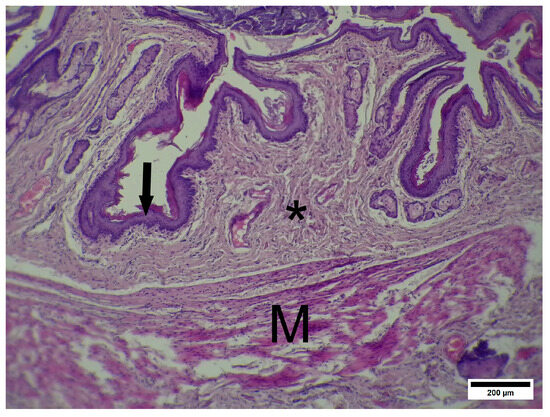

Combined Tribenoside/Lidocaine Rectal Cream (Procto-Glyvenol®) Promotes Tissue Repair in a Preclinical Model of Acute Complicated Anal Fissure

by Ganna Zaychenko, Nazarii Kobyliak, Larysa Natrus, Maksym Tymofieiev, Patrizia Angelico, Stefano Biondi and Matteo Malinverno

Background/Objectives: The objective of this study was to evaluate the efficacy of a rectal cream containing tribenoside and lidocaine (TL) in a rat model of anal fissure (AF) and to investigate the potential mechanisms of its therapeutic action compared with those of [...] Read more.

Background/Objectives: The objective of this study was to evaluate the efficacy of a rectal cream containing tribenoside and lidocaine (TL) in a rat model of anal fissure (AF) and to investigate the potential mechanisms of its therapeutic action compared with those of a standard care rectal cream containing 2% diltiazem (D). Methods: Treatment efficacy was assessed via macroscopic methods. The levels of the inflammatory factors IL-6 and IL-10 in the tissues were measured via ELISA. Histology assessment was performed with standard hematoxylin/eosin stain, Masson’s trichrome method and picrosirius stain. The levels of NF-κB, VEGF, TGF-beta 1, HIF-1α and E-cadherin were measured via densitometric immunoblot analysis. Results: The results of this study show that the medical product TL has therapeutic efficacy in a preclinical model of acute complicated AF, which is likely related to its complex composition. The severity of pathology in the TL group was significantly lower than that in the control pathology (CP) group on the eighth day of treatment and remained significantly lower on the 11th and 12th days. There was no statistically significant difference between the TL group and the CP group (p = 0.186 for IL-6 and p = 0.078 for IL-10). The efficacy of TL and D groups showed no statistically significant difference. At the end of the experiment, after 12 days of treatment, the level of the proinflammatory marker NF-κB in the CP group was greater than that in the intact control (IC) group. In turn, the NF-κB level in the TL group was lower than that in the CP group and significantly lower than that in the D group. Other important markers evaluated in this study demonstrated a similar tendency. The histopathological analysis showed that TL ointment promoted superior tissue repair, resulting in healthier anodermal architecture with minimal scarring and reduced fibrosis. Conclusions: This study confirms the potential for conducting further pharmacological studies of the mechanism of action and further clinical trials of the rectal cream TL, which has certain advantages in terms of effectiveness in a model of acute complicated AF. Full article